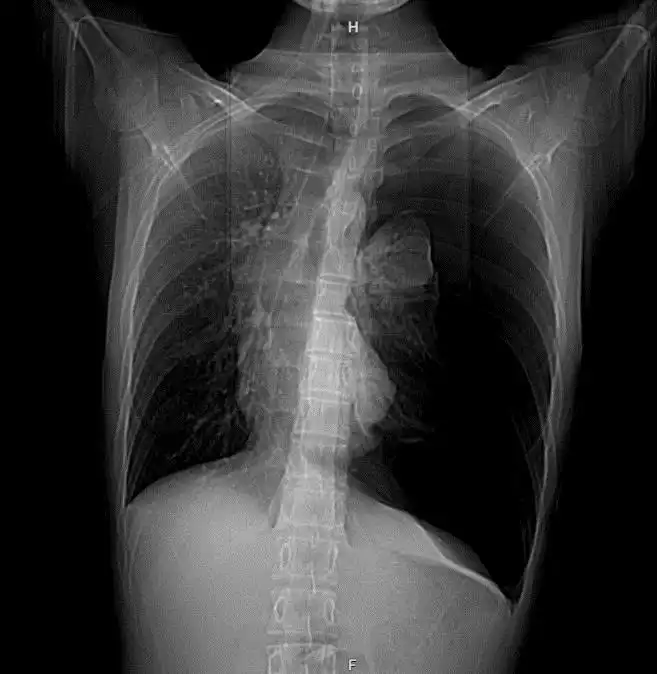

X-quang ngực và cắt lớp vi tính (CLVT) tại thời điểm nhập viện: Ghi nhận hình ảnh tràn khí màng phổi trái lượng nhiều, gây xẹp nhu mô phổi trái và đẩy lệch trung thất sang bên đối diện.

| Hình ảnh: Xquang, CLVT lúc vào viện: Hình ảnh tràn khí màng phổi số lượng lớn gây đè ép nhu mô phổi trái và trung thất. | |